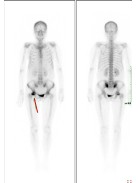

病例三:寻找肿瘤的原发病灶:骨肉瘤

男性,32岁,如图所示:红色箭头标志为可见患者右侧胫骨上段改变,考虑为恶性骨肿瘤。